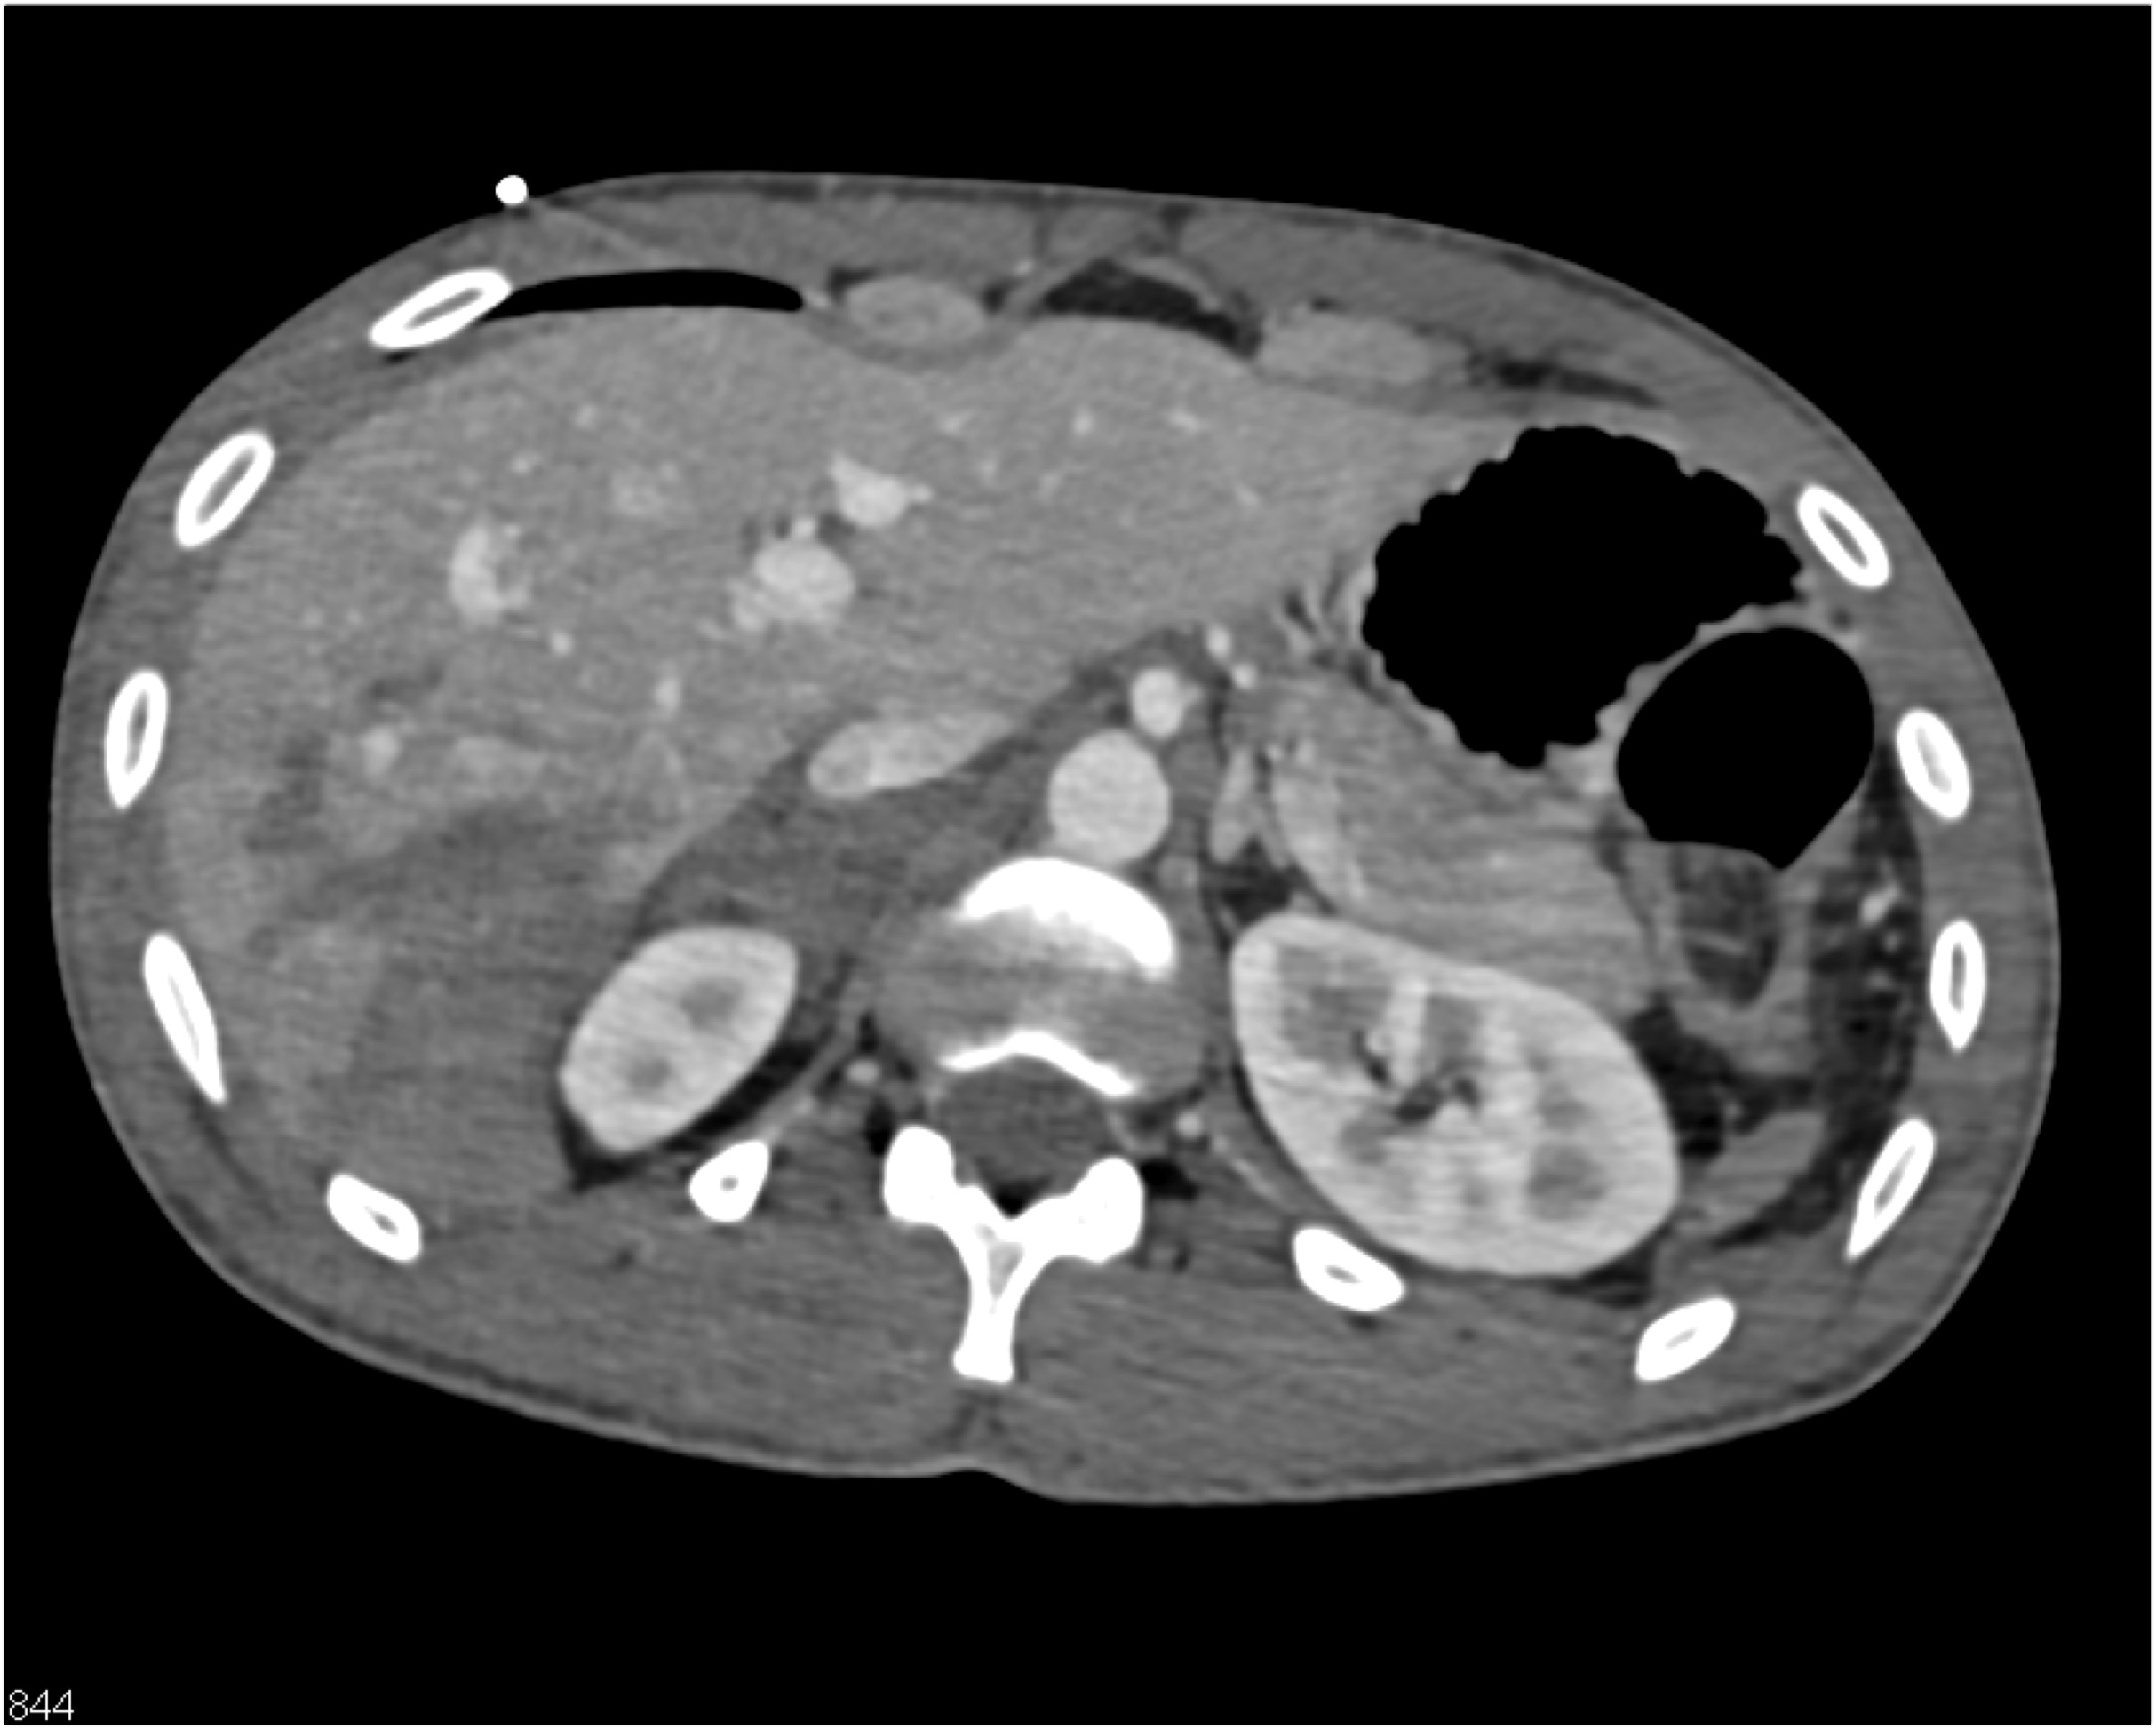

5) In this patient with Crohn’s disease and abdominal pain the critical CT finding is

stricture of colon

bowel wall thickening

active GI bleed

superimposed colon cancer